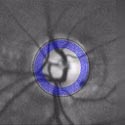

Here are retina images from twins / Ci-dessous deux rétines de jumeaux:

Jumeaux 1 Jumeaux 2

A kind of (circular) barcode is extracted from the pattern of blood vessels, which is stored for further comparison with a new retina image.

Une sorte de code à barres (circulaire) est extrait du réseau vasculaire, qui est stocké afin de permettre plus tard une comparaison avec une nouvelle image de rétine.

First the intensity profile is extracted, then a circular scan is performed to locate blood vessels.

Les lignes de plus fortes intensités sont d'abord extraites, puis un scan circulaire permet d'identifier la localisation des vaisseaux sanguins.